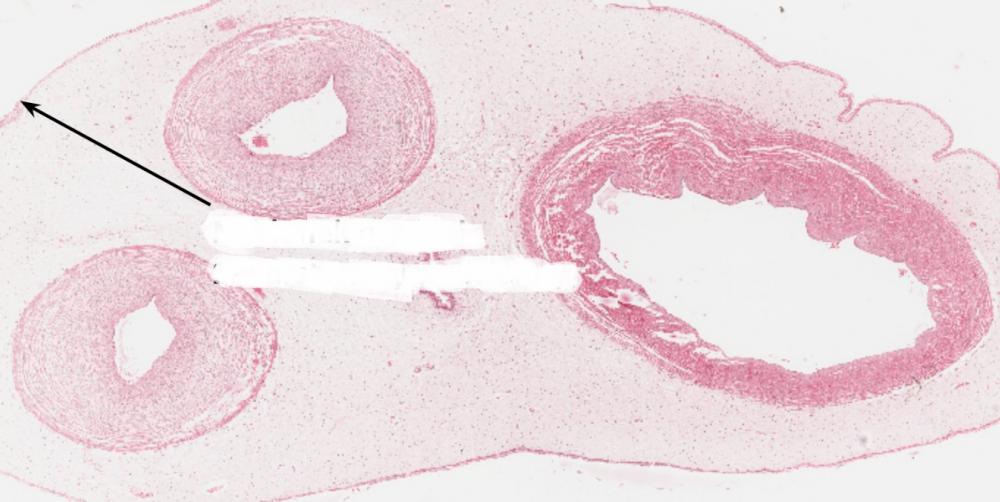

tętnice (pępowina)

żyła (pępowina)